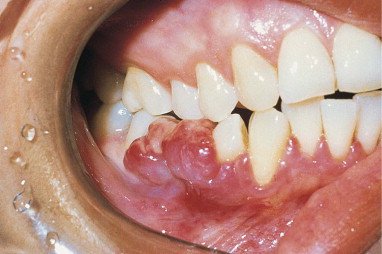

🔴NON SPECIFIC CONDITIONED ENLARGEMENT (PYOGENIC GRANULOMA)

● Female are affected more than male

● Common age of occurrence is 11-40 yrs

● Its size ranges from 0.9- 2 cm.

● Asymptomatic, may be papular or nodular Polypoid mass.

● It may become mature and becomes less vascular and more collagenous gradually converting into a fibrous epulis.

● Lesions are elevated pedunculated or sessile masses with smooth lobulated or even warty.

● Surface is commonly ulcerated and shows tendency to hemorrhage upon slightest pressure or trauma

● Variegated red and white pattern